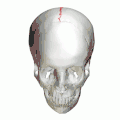

Animation. Sagittal suture shown in red. -